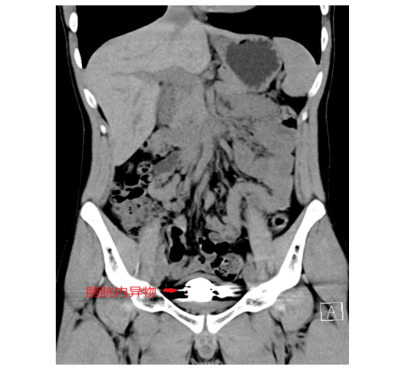

近日,长沙中心立博体育 (南华大学附属长沙中心立博体育 )泌尿外科成功为一名22岁男性患者实施微创手术,一次性从其膀胱内取出50颗磁性钢珠。该病例因异物数量多、滞留时间长,手术难度较高,经医疗团队精细操作,患者术后恢复良好,目前已康复出院。医生提醒:磁性玩具安全隐患大,切勿随意置入体内。

)泌尿外科就医,经影像学检查发现,其膀胱内竟积聚大量直径约5毫米的金属圆珠,排列紧密且表面已形成钙化外壳。该院泌尿外科一区主任傅发军及其团队结合病史及临床经验判断异物为数十颗磁性钢珠,如不及时取出,长期滞留可能导致尿路梗阻、感染甚至组织损伤。

由于异物数量多、磁性强且表面光滑,传统开放手术创伤较大,团队研究后决定采用“经尿道膀胱镜钬激光碎石取异物术”。手术需克服三大难点:磁珠相互吸附难以分离、表面光滑不易抓取、膀胱壁脆弱易损伤。医疗团队通过精准影像定位和精细操作,历时2小时成功取出全部异物,共计50颗磁性钢珠。术后患者症状立即缓解,恢复顺利。